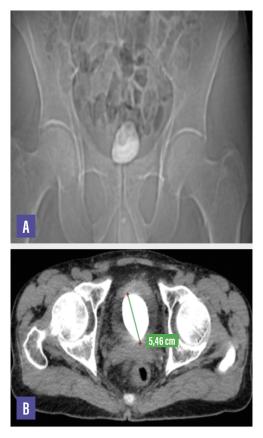

Une radiographie de l’abdomen sans préparation centrée sur le bassin montre une opacité de tonalité calcique occupant l’aire vésicale (fig. A). Un scanner abdomino-pelvien sans injection de produit de contraste est réalisé afin de mieux analyser cette masse  ; il permet de visualiser une lithiase vésicale occupant la quasi-totalité de la vessie et mesurant 55 × 45 mm avec 1 120 UH de densité (fig. B).

Le patient n’a pas de lithiase rénale ni urétérale. Il a bénéficié d’une fragmentation du calcul avec extraction des fragments par voie transurétrale.